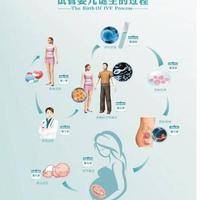

试管5bb基本不会分裂,这是因为5bb囊胚的内部已形成高度分化的内细胞群和外细胞群,细胞连接紧密,不会自行分裂;其次是移植后囊胚已进一步分化,各自承担不同发育任务,是不会在进一步变化的;最后,它们的遗传物质已经稳定,不会轻易出现改变的。

5bb囊胚的数字“5”代表囊胚的发育阶段,并处于较高的发育水平;第一个“b”表示内细胞团质量良好,细胞数目适中且排列紧密;第二个“b”表示滋养层细胞质量同样良好,细胞层数适中且结构完整。可以看出囊胚是中等偏上质量的胚胎,具有较高的移植成功率和发育潜力。很多患者就以为这个囊胚在移植后是可以分裂的,实际上,多数情况下都是不会的,这主要是因为:

综上所述,5BB胚胎不会无限制地分裂,这是由其生物学特性和发育阶段所决定的。在试管治疗中,我们应该关注5BB胚胎的质量而非分裂,通过实时监测和优化培养条件,选择建议的移植时机,以提高移植成功率,确保自己能够成功怀上健康的孩子。